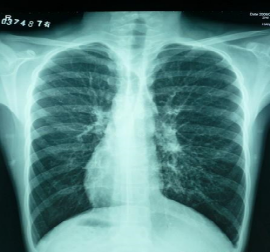

(4)胸腔积液:准备一个胸腔积液患者,三张CT片(一张少量、一张中量、一张大量),解释胸腔积液的发展过程及体格检查结果改变过程。并为胸腔穿刺术做一点铺垫。(8min)